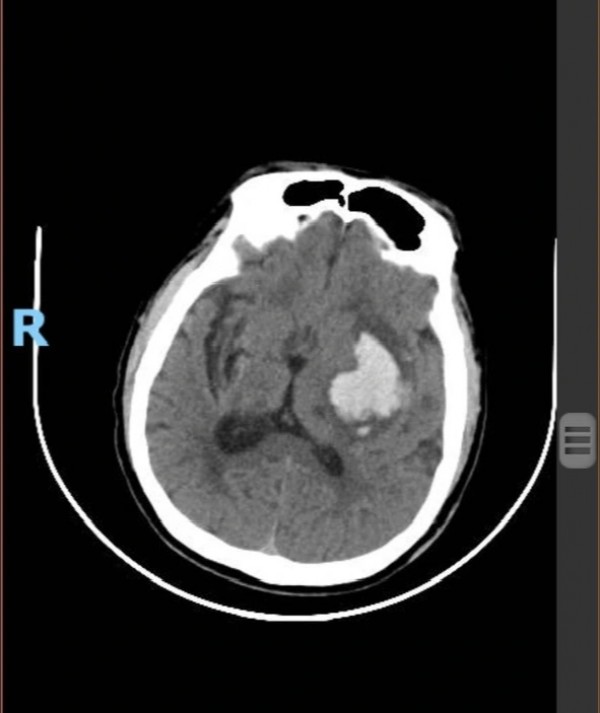

Kết quả chẩn đoán hình ảnh cho thấy nam tài xế bị xuất huyết não bán cầu trái rất nặng